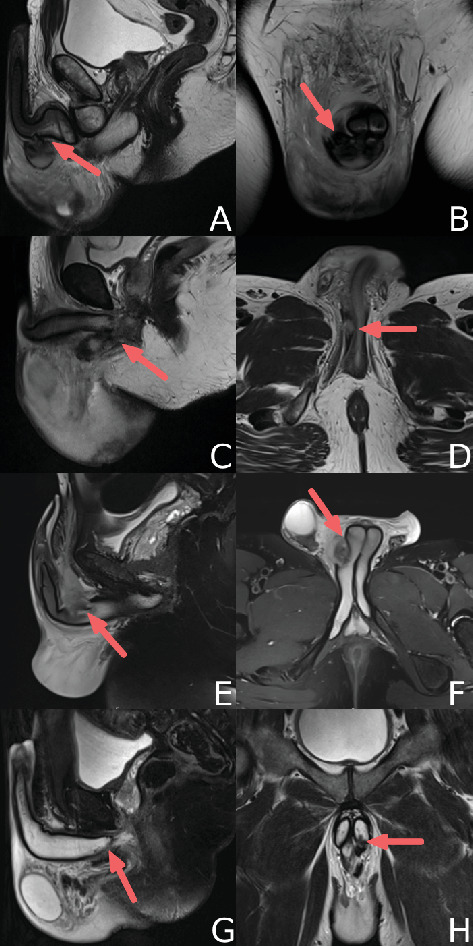

本病例系列介绍4例阴茎海绵体内体(EPICC)极近端骨折。患者年龄33-53岁,主要在性交期间出现阴茎外伤,表现出不典型症状,阴茎完好,但会阴和阴囊明显挫伤。通过阴茎磁共振成像(MRI)确诊,显示阴茎基部骨折。所有患者均通过会阴中线切口进行手术修复,无长期并发症报道。这一系列研究强调了MRI在诊断非典型骨折中的价值,并支持会阴手术入路对外外阴骨折进行最佳暴露和修复。

This case series presents four cases of extreme proximal internal corpus cavernosum (EPICC) penile fractures. Patients, aged 33-53, presented with penile trauma primarily during sexual intercourse, exhibiting atypical symptoms sparing the penis but with significant perineal and scrotal bruising. Diagnosis was confirmed via penile magnetic resonance imaging (MRI), revealing fractures at the penile base. All patients underwent surgical repair through a midline perineal incision, with no long-term complications reported. This series highlights the value of MRI for diagnosing atypical fractures and supports a perineal surgical approach for optimal exposure and repair in EPICC fractures.